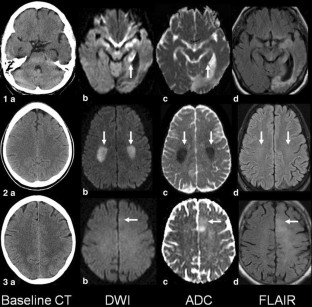

Fig. 1